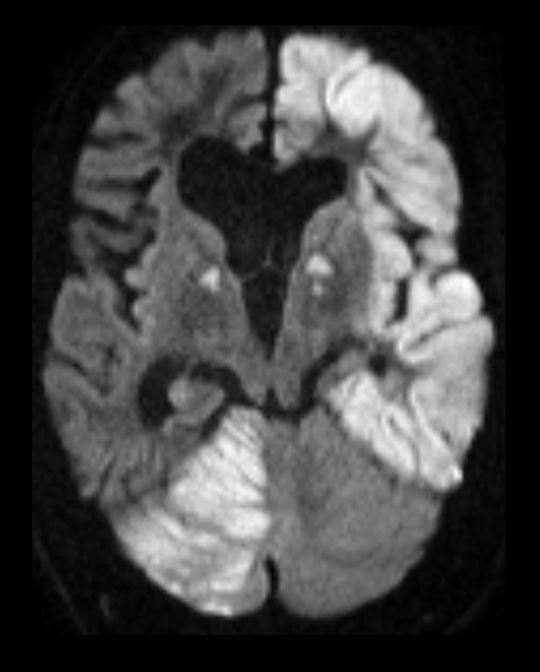

To dager senere fikk pasienten kortvarige fokale anfall i serie med hodedreining mot høyre og høyresidige rykninger. Anfallene ble forsøkt kupert med valproat i bolus og infusjon – uten hell. Pasienten ble lagt i barbituratnarkose og overflyttet til universitetssykehus, hvor man hevet sedasjonen påfølgende dag. Han forble imidlertid komatøs, og det ble derfor gjort MR-undersøkelse av hjernen. Den viste utbredte områder med redusert diffusjon som tegn på cytotoksisk ødem kortikalt i venstre storehjernehemisfære, i basalganglier, i thalamus bilateralt samt i høyre lillehjernehemisfære. Pasienten ble på ny sedert for å avlaste hjernen og forebygge videre utvikling av hjerneødemet. Etter noen dager med intensivbehandling våknet han gradvis opp etter at sedasjonen ble stoppet. MR-kontroll viste noe tilbakegang av forandringene.

MR-forandringene på bildet illustrerer nevroanatomien med det fokale utgangspunktet i venstre storhjernehemisfære. Signalene forplanter seg til thalamus og basalganglier bilateralt og til kontralaterale lillehjernehemisfære via kryssede og ukryssede aksonale baner.